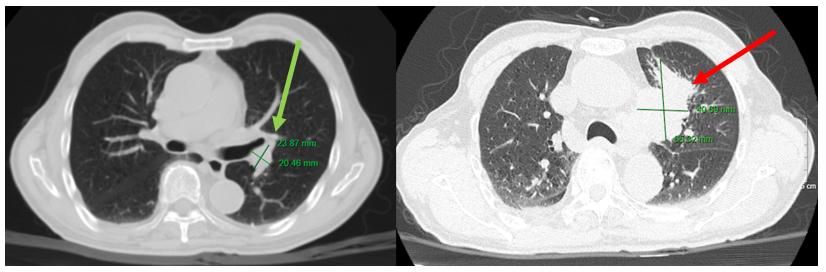

Hình 6. Hình ảnh khối u phổi trái với kích thước 21x16 mm (đang điều trị, mũi tên xanh), tăng kích thước lên 60x42 mm (sau khi bỏ điều trị 3 tháng, mũi tên đỏ) trên phim chụp cắt lớp vi tính lồng ngực, cửa sổ trung thất.

Hình 7. Hình ảnh khối u phổi trái với kích thước 21x16 mm (đang điều trị, mũi tên xanh), tăng kích thước lên 60x42 mm (sau khi bỏ điều trị 3 tháng, mũi tên đỏ) trên phim chụp cắt lớp vi tính lồng ngực, cửa sổ nhu mô.